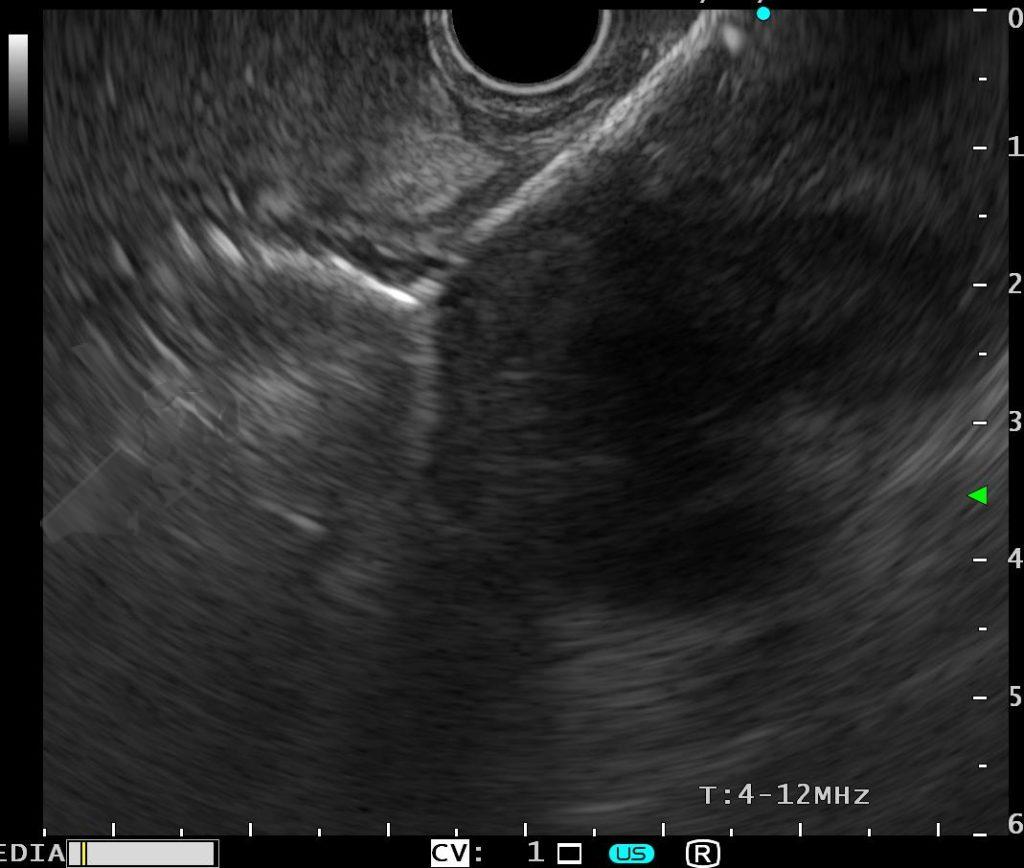

O principal método de drenagem biliar para obstruções malignas distais é a CPRE. Nos casos de impossibilidade/falha, a coledocoduodenostomia ecoguiada (EUS-choledoduodenostomy – CDS) surge como uma das principais opções, porém pode ser desafiadora devido fatores anatômicos, como colédoco < 12 mm, posição do colédoco distante do probe, além da possibilidade de disfunção do stent a longo prazo (1 – 3). Considerando um ducto cístico patente, a drenagem ecoguiada da vesícula (EUS-gallblader drainage – GBD) é uma alternativa interessante, pela técnica em geral mais fácil (alvo/vesícula de maiores proporções). Uma vez que os resultados são bons (100% de sucesso técnico e 10,8% de eventos adversos em um estudo), os autores optaram por investigar estas opções como primeira linha na paliação endoscópica da obstrução maligna distal (4, 5).

Trata-se de um estudo retrospectivo multicêntrico que incluiu casos de EUS-CDS e GBD como tratamento de primeira linha para drenagem biliar (sem tentativa de drenagem por CPRE). Foram incluídos pacientes com ducto cístico patente (avaliação prévia por RNM e/ou TC e durante a ecoendoscopia terapêutica), ambos métodos factíveis no procedimento inicial, colédoco > 12 mm e não candidatos a cirurgia.